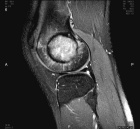

Patient is a 20 y/o male with a history of L. knee GCT s/p excision 11 months ago.

He presents w/ increasing L. knee pain; PMH: GCT; PE L. knee with no effusion + tenderness to palpation over lat. fem. condyle; + tenderness w/ PROM 0-95